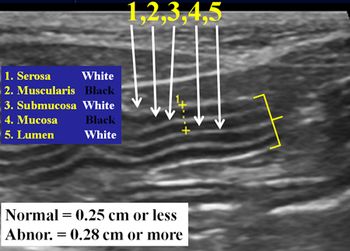

What to look for when evaluating cats for small bowel disease as a cause of chronic vomiting.